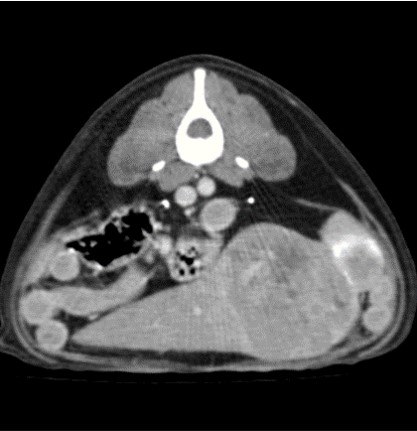

CT 검사

CT는 신체의 여러 각도에서 x-선을 투과시킨 후 단면 영상과 3차원적 입체영상을 얻을 수 있어 해부학적 구조와 병적 변화 정도를 정확하고 빠르게 평가할 수 있습니다.

CT 검사는 각종 종양과 염증, 외상 및 신체 기형과 같은 질환의 진단에 유용하게 사용될 수 있으며 수술이 지시되는 경우에도 진단을 넘어 정확한 해부학적 구조의 평가가 가능해져 이를 통해 수술 계획을 수립할 수 있습니다.

건국대학교 동물암센터에서 보유하고 있는 CT는 여러 개의 디텍터를 갖고 있는 multi-detector CT (MDCT)로써 촬영 시간 및 피폭량을 최소화 할 수 있는 장점이 있습니다. 여러 개의 디텍터를 통해 선명한 영상을 빠르게 구현해 냄으로써 진단의 정확성을 높일 수 있습니다.

대표질환

- 종양 진단 (두경부, 흉강, 복강, 사지 골격) 및 전이 평가

- 골격계 질환 및 골절 합병증 평가

- 혈관 기형 (PDA, PSS, vascular ring anomaly 등)

- 척추 질환 (척추 골절, hemivertebra)

- 폐 질환

간 종양 -

비장종양 -

두경부 종양 -

척추질환